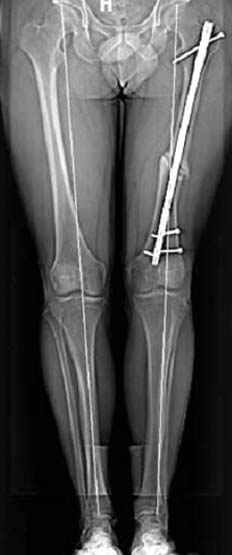

N3 рисунок окончательный снимок, после операции моя рентгенограмма должен выглядеть примерно как эта картина. На N4 снимке клин перед удалением; N5 послеоперации 3 нед.; N6 окончательная рентгенограмма.

Интересно бы посмотреть рентгенограмму таза (оба сустава) а также рентгенгорамму с захватом коленных суставов (по Dror Paley).